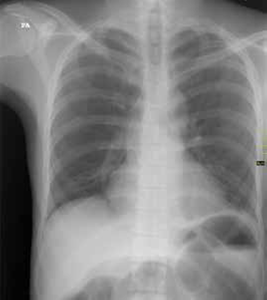

Entre sus exámenes de laboratorio se destacaba una hipopotasemia leve; en el estudio de radiología simple de abdomen, en bipedestación y posición supina, se observó un patrón de ‘pilas de monedas’ (figuras 1, 2, 3).